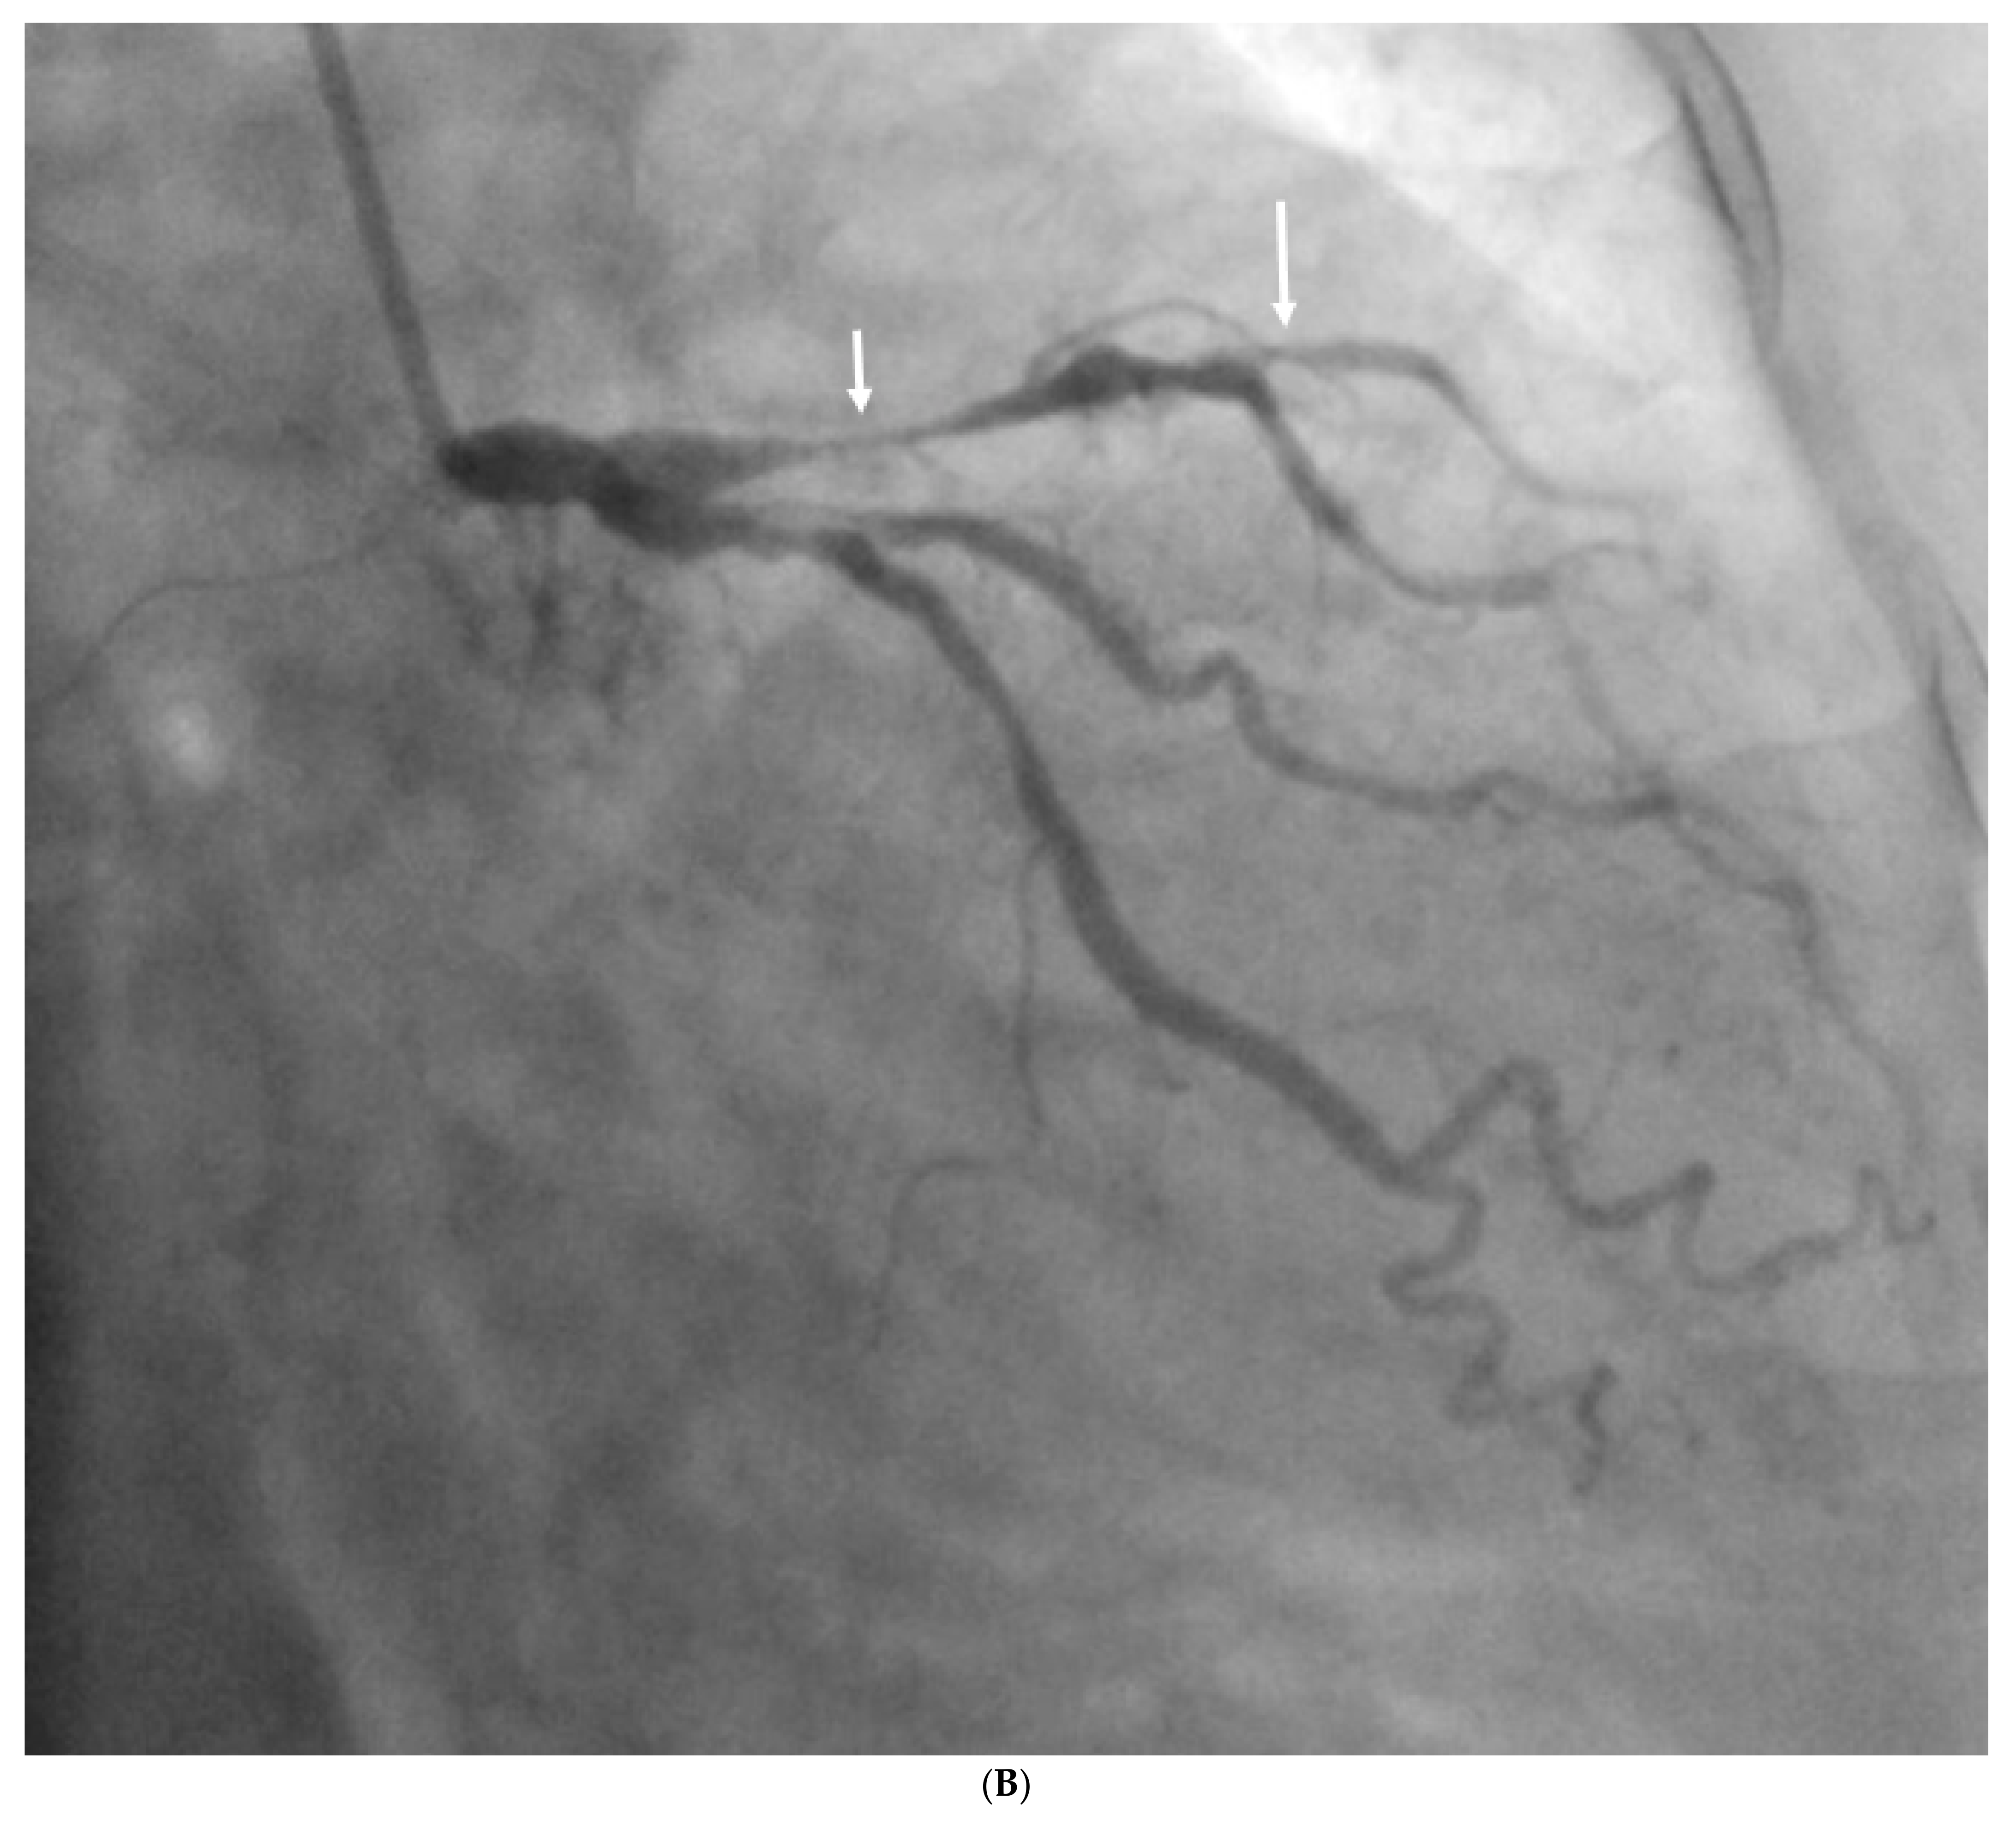

- Sun, Z.; Ng, C.K. Artificial intelligence (enhanced super-resolution generative adversarial network) for calcium deblooming in coronary computed tomography angiography: A feasibility study. Diagnostics 2022, 12, 991. [Google Scholar] [CrossRef]

- Sun, Z.; Ng, C.K. Finetuned super-resolution generative adversarial network (artificial intelligence) model for calcium deblooming in coronary computed tomography angiography. J. Pers. Med. 2022, 12, 1354. [Google Scholar] [CrossRef]

- Ng, C.K.; Sun, Z.; Jansen, S. Comparison of performance of micro-computed tomography (Micro-CT) and synchrotron radiation CT in assessing coronary stenosis caused by calcified plaques in coronary artery phantoms. J. Vasc. Dis. 2023, 2, 338–350. [Google Scholar] [CrossRef]

- Sun, Z.; Xu, L.; Fan, Z. Coronary CT angiography in calcified coronary plaques: Comparison of diagnostic accuracy between bifurcation angle measurement and coronary lumen assessment for diagnosing significant coronary stenosis. Int. J. Cardiol. 2016, 203, 78–86. [Google Scholar] [CrossRef] [PubMed][Green Version]